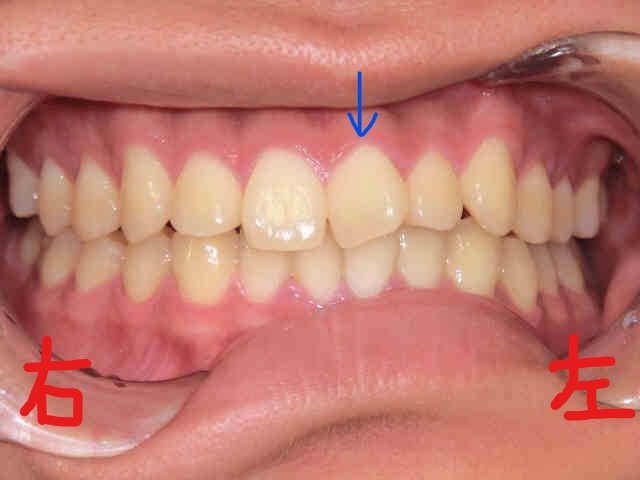

上段の写真が矯正開始前、下段の写真が矯正終了直後のものです。

患者様は、左上の前歯(青色矢印)の“歪み(捻転)”を以前から気にされており、当院まで遠方よりご来院くださいました。